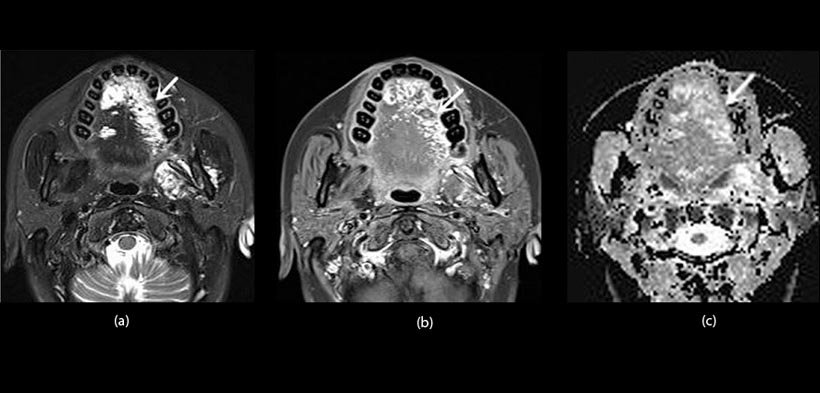

Fig. 2. Paciente femenino de 43 años de edad con una malformación vascular en la lengua. (a) vista axial en T, imagen ponderada con supresión de grasa muestra múltiples lesiones heterogéneamente hiperintensas (flecha) en el dorso de la lengua. (b) Imagen con mayor contraste, vista axial de RM ponderada en T1 con supresión grasa demuestra realce heterogéneo (flecha). (c) coeficiente de difusión aparente (ADC) revela heterogéneamente lesiones hiperintensas (flecha). El valor ADC es 1.51x103mm2s-1.